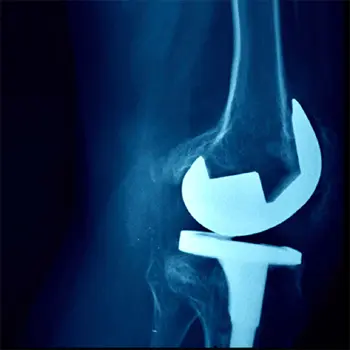

Chronic knee pain can make even simple tasks—walking, climbing stairs, sitting, or standing—extremely difficult. At HappyKnees, we offer advanced Primary Knee Arthroplasty in Malad, performed by leading orthopedic specialist Dr. Akash Saraogi. This procedure, also known as Primary Knee Replacement, involves replacing the damaged knee joint with high-quality artificial implants to restore smooth, pain-free movement.

Primary knee arthroplasty is a surgical procedure in which the damaged surfaces of the knee joint are replaced with artificial implants to relieve pain, correct deformity, and restore smooth movement.

Yes. Modern knee replacement surgery is highly safe, advanced, and predictable. With minimally invasive methods and high-precision implants, risks are minimal and recovery is faster than ever.